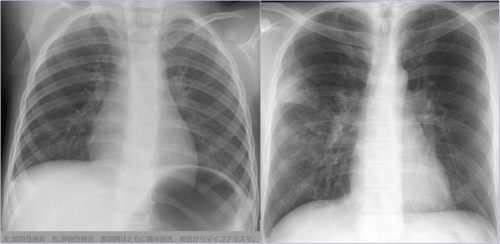

[区域性分布と非区域性分布の理解] ***下図を参考に大葉性・小葉性と区域性・非区域性を混同しないこと。 [マイコプラズマ肺炎陰影の成り立ち] [参考1]マイコプラズマ肺炎の2型 [参考2]マイコプラズマ肺炎の2型 [参考3]マイコプラズマ肺炎(肺胞性間質性)

右肺下肺野では肺胞性陰影(浸潤影・airbronchogram)と間質性陰影(水平裂外側の下方への偏移・tram line・線状影等)が混在している。 [参考]右肺は均等影様にみえるが左肺と同じ透過性不良のすりガラス様陰影で間質性の陰影。 [びまん性肺病変の基本型] びまん性肺疾患 間質性陰影と肺胞性陰影